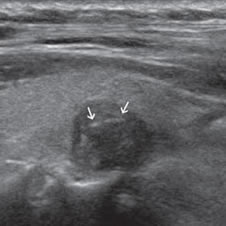

Un nódulo que tiene un componente quístico significativo, usualmente es un nódulo benigno hiperplástico, que ha acumulado abundante coloide (Figura 2a) o bien, un nódulo sólido que ha experimentado un proceso de degeneración colicuativa o hemorragia (Figura 2b). El coloide o el contenido líquido de un nódulo se ve anecogénico (negro en la imagen ecográfica) y las estructuras sólidas se ven ecogénicas (distintos tonos de grises), siendo la ecogenicidad similar al del parénquima tiroideo. En un nódulo sólido la ecoestructura y la ecogenicidad pueden ser variables. En general, la frecuencia de carcinoma es muy baja en nódulos quísticos13 y la mayoría de los carcinomas se presentan como nódulos sólidos (Figura 2c).

Figura 2. a) Quiste coloideo anecogénico y focos ecogénicos (flecha) con artefacto en cola de cometa; b) Nódulo mixto sólido-quístico (cabezas de flechas). Imagen vegetante (flecha) adherida a un tabique que se proyecta al lumen; c) Comparación entre el aspecto ecográfico de un cáncer papilar sólido (flecha abierta) y un quiste coloideo anecogénico.